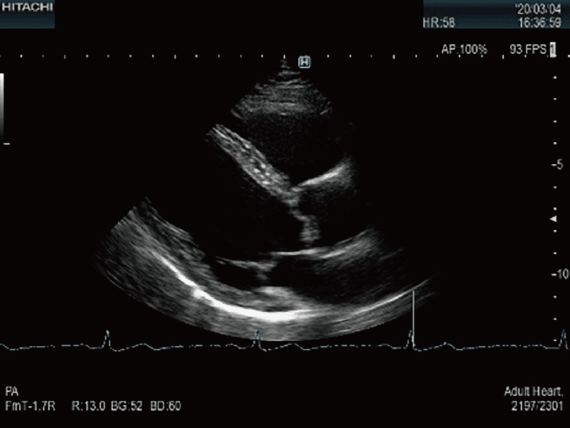

心臓超音波検査

胸部より超音波を照射し,動いている心臓の内部構造を描出し,心臓の動きを動画として観察する検査です。心臓弁膜症や虚血性心疾患,心筋症などの診断に用いられます。治療方法の選択や治療効果の判定,手術時期の決定などに役立ちます。